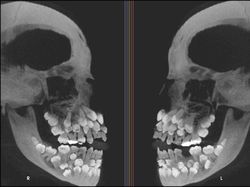

Penampakan seseorang yang mengalami Hyperdontia, merupakan kondisi mulut yang ditandai dengan jumlah gigi yang berlebih, di mana seseorang memiliki lebih dari 20 gigi primer atau lebih dari 32 gigi permanen. (Foto: Brightside)